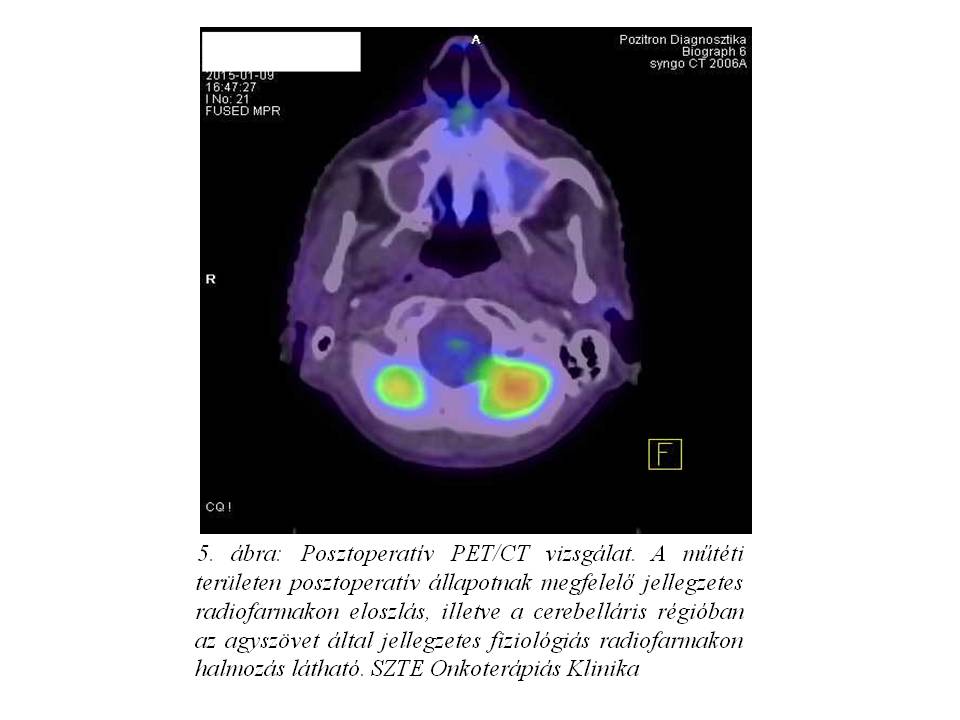

Staging komplettálás céljából PET/CT vizsgálat történt.

A PET/CT vizsgálat (4. ábra, 5. ábra) sem a műtéti területen, sem más lokalizációban nem igazolta FDG-avid (FDG=fluorodeoxiglükóz), kóros halmozású tumorszövet jelenlétét.